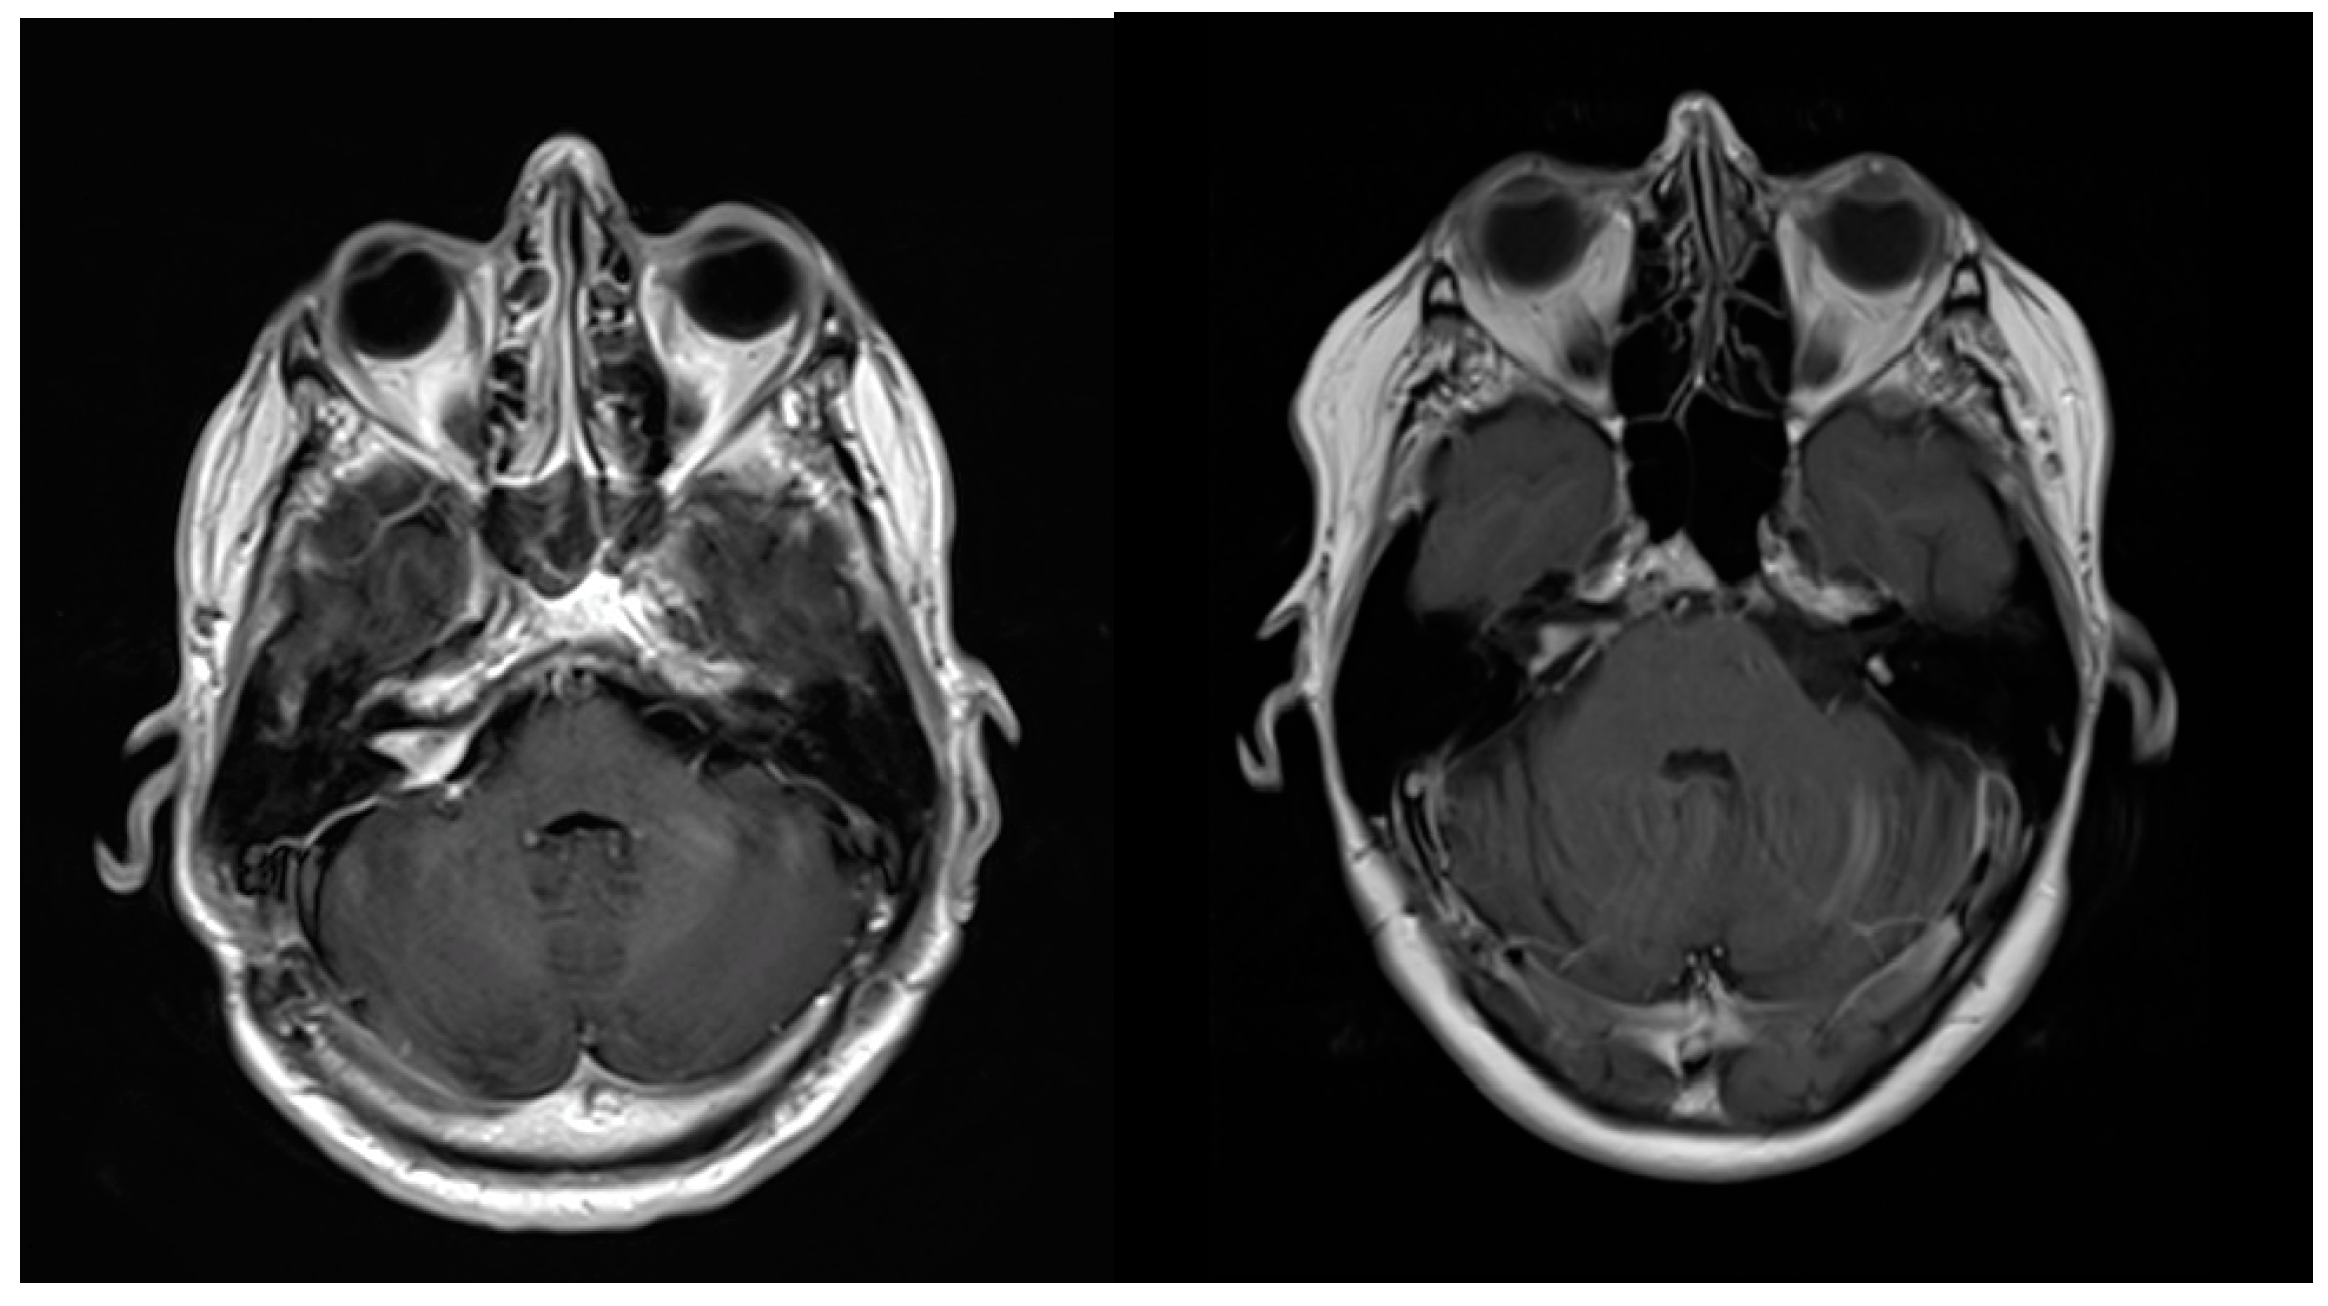

| 1. | 4 | 4 | 10.2 | 15.0 | 1.9 | 1.7 | 12 | 8.1 | + | solid | 32 | 42 |

| 2. | 3 | 4 | 3.2 | 4.4 | 1.2 | 0.4 | 12 | 6.8 | - | solid | 12 | 26 |

| 3. | 4 | 4 | 4.7 | 12.3 | 1.1 | 0.8 | 12 | 9.9 | - | necrosis | 24 | 36 |

| 4. | 4 | 4 | 4.5 | 8.3 | 0.3 | 0.03 | 12 | 5.6 | + | cystic | 24 | 84 |

| 5. | 4 | 4 | 7.7 | 9.4 | 2.2 | 1.9 | 12 | 7.6 | - | necrosis | 24 | 36 |

| 6. | 4 | 4 | 8.2 | 11.7 | 1.6 | 1.2 | 12 | 8.5 | + | necrosis | 24 | 38 |

| 7. | 3 | 4 | 3.9 | 7.7 | 1.2 | 0.5 | 12 | 6.2 | - | solid | 18 | 52 |

| 8. | 4 | 4 | 5.0 | 10.3 | 2.1 | 1.1 | 12 | 7.5 | - | necrosis | 27 | 46 |

| Mean: | 3.75 | 4 | 5.9 ± 2.5 | 9.9 ± 3.2 | 1.5 ± 0.6 | 0.9 ± 0.6 | 12 | 7.5 ± 1.4 | - | - | 22 ± 5.9 | 45 ± 17.5 |